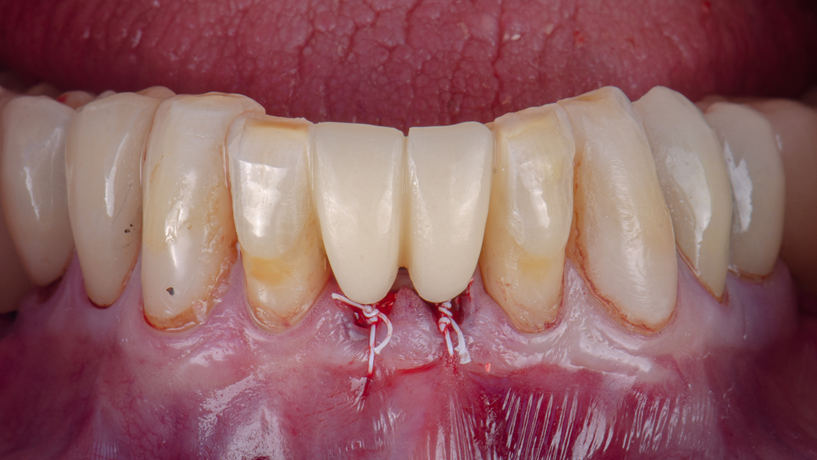

Sutura e provisório pós-operatório

Após o preenchimento dos GAPs com enxerto, foi realizada a sutura visando estabilizar os tecidos e proteger o coágulo. Utilizou-se fio de PTFE (politetrafluoretileno) monofilamentar (Cytoplast – Implacil Osstem), material não reabsorvível altamente indicado em situações de tecidos finos ou áreas de regeneração óssea. Esse tipo de fio de sutura apresenta baixa aderência bacteriana e é biologicamente inerte, gerando mínima reação inflamatória nos tecidos. Tais propriedades são desejáveis para garantir uma cicatrização previsível, pois reduzem o risco de infecção do sítio cirúrgico e evitam isquemia marginal por excesso de tensão. O fio de PTFE também possui superfície lisa (baixo coeficiente de atrito) e boa maleabilidade, deslizando facilmente no tecido e facilitando a obtenção de nós firmes. No presente caso, isso permitiu manter as papilas suturadas com estabilidade, sem irritação aos tecidos – uma consideração importante dada o periodonto fino da região anterior inferior.

No pós-operatório imediato, a paciente recebeu um provisório fixo, confeccionado previamente de forma digital e executado em impressora 3D. Trata-se de uma prótese adesiva provisória impressa em resina, projetada para substituir os incisivos ausentes sem necessidade de apoiar-se sobre os implantes recém-colocados. Essa prótese possuía extensões em forma de aletas que foram cimentadas na face lingual dos dentes 32 e 42, previamente condicionados e discretamente preparados para receber as abas. A opção por um provisório adesivo colado aos dentes adjacentes traz diversas vantagens neste contexto: (1) preservação do implante em osseointegração: evita-se aplicar carga ou microtrauma sobre os implantes imediatos durante seu período crítico de cicatrização, uma vez que a prótese não exerce pressão sobre a região enxertada; (2) conforto e estética imediata: a paciente sai da cirurgia já com elementos dentários na região anterior, melhorando a fonética, estética do sorriso e a auto-estima, sem necessidade de prótese removível; (3) simplicidade e minimamente invasivo: o preparo nos dentes 32 e 42 foi leve, restringindo-se ao necessário para acomodação das aletas, preservando em grande parte a estrutura dental. Em resumo, o provisório adesivo funcionou como uma excelente solução transitória, protegendo o sítio cirúrgico enquanto devolvia função mastigatória leve e estética satisfatória no período de espera pela reabilitação definitiva.